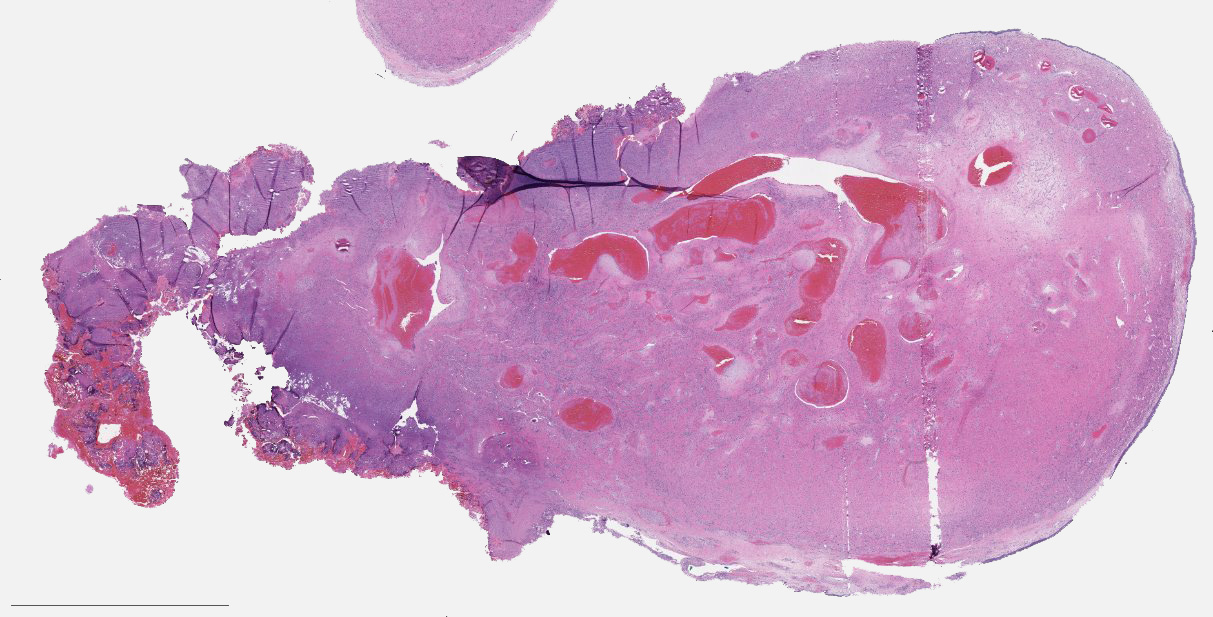

Microscopic (histologic) description

- Benign fibrovascular lesion composed of 2 components

- Vascular space of various sizes, ranging from dilated branching vessel of various thickness to slit-like capillaries

- Fibrous or collagenous stroma with fibroblasts

- Central area of the tumor is typically cellular, composed of fibroblasts or myofibroblasts with spindle, round or stellate morphology

- Stroma can be fibrous, edematous or collagenized

- Fibrinous thrombi may be seen in dilated vessels

Microscopic (histologic) images

Contributed by Bin Xu, M.D., Ph.D.

Contributed by Kelly Magliocca, D.D.S., M.P.H.